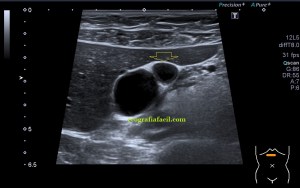

Bien, hemos visto una lesión que es un quiste hidatídico calcificado, pero te preguntarás, si nunca viste uno, ¿cómo es uno cuando tiene «hijas»?, es decir, cuando está activo…Mira este corte transversal de un hígado:

La LOE es de aspecto redondeado, heterogéneo, con multitud de pequeñas imágenes anecoicas e hipoecogénicas, de diferentes tamaños. Esta lesión fue estudiada también mediante otra técnica de imagen, la RMN donde se observa una imagen hiperdensa, con una amalgama de lesiones bordeando a periferia de la misma, de distintos tamaños como se objetiva en la imagen del mismo paciente, de la ecografía inmediatamente superior (Imagen 7). La lesión es activa, por tanto debió de ser tratada, la patología es potencialmente mortal en caso de que el quiste se rompiese.